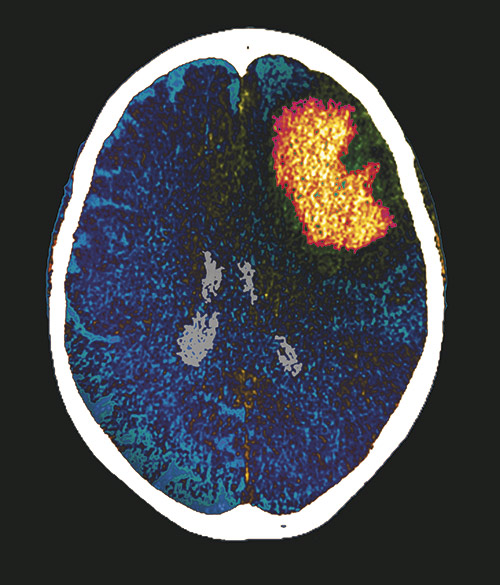

Tidlig kirurgi ved hjerneblødning?

Tidlig kirurgi etter mellomstore hjerneblødninger gir ikke bedre funksjonsnivå etter seks måneder enn konservativ behandling.

Hjerneblødninger som gir forhøyet intrakranialt trykk ledsaget av fallende bevissthet behandles gjerne operativt på vital indikasjon, mens små blødninger hos våkne pasienter behandles konservativt. Hvordan de som faller mellom disse kliniske ytterpunktene skal behandles, har lenge vært omdiskutert. I multisenterstudien STICH II ble over 600 våkne pasienter med overflatiske, mellomstore hjerneblødninger randomisert til enten tidlig kirurgi eller konservativ behandling (1). Etter seks måneder var det ingen gevinst av tidlig kirurgi når det gjaldt funksjonsnivå. Det var en ikke-signifikant forskjell i overlevelse, idet henholdsvis 18 % og 24 % i hver gruppe på det tidspunkt var døde (p = 0,095).